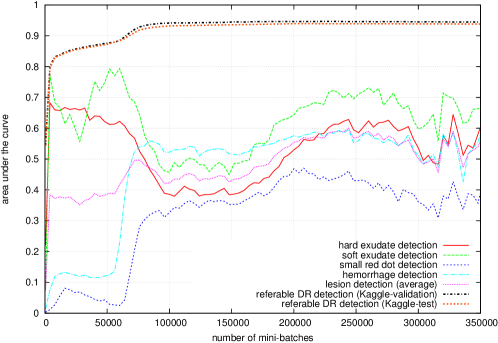

Figure 5 reports the performance of ‘net B’ at different checkpoints stored during the training process. The hue-constrained sensitivity criterion is used, with or without sparsity maximization. Performance at the image level was assessed using a ROC analysis in the validation subset of Kaggle-train (‘Kaggle-validation’ for short), as well as in Kaggle-test: the area under the ROC curve is used as performance metric. Performance at the lesion level was assessed using a free-response ROC (FROC) analysis in the DiaretDB1 dataset. FROC curves are usually not bounded along the x-axis (the number false positives per image): we used as performance metric the area under the FROC curve for , divided by (with = 10). Performance is computed for each lesion type independently, and an average performance metric is also computed. The influence of , the factor of the cost function, on the performance at the image level ( in the Kaggle validation set) and at the lesion level ( in the DiaretDB1 dataset), is given in table 2.

As commonly done in machine learning competitions (Russakovsky et al., 2015), an ensemble of ConvNets was used to boost performance. As less commonly done, all ConvNets in the ensemble originate from the same network, but with parameter values obtained at different checkpoints during the learning process. This way, training the ensemble is not significantly more computationally intensive than training a single ConvNet. As shown in Fig. 5, individual lesion types are not optimally detected after the same number of iterations. So, the idea was to export parameter values from the ConvNet when:

Besides analyzing the pixel-level performance of the final ConvNets, we also analyzed the pixel-level performance while the ConvNets are being trained (see Fig. 5 for the ‘net B’ ConvNet). It turned out to be quite instructive. By analyzing performance at the image level alone (the area under the ROC curve in the Kaggle validation set), all we can see is that 1) performance quickly reaches a satisfactorily level (), then 2) slowly increases for many iterations, 3) experiences a second leap to reach a very high level () and finally 4) reaches its optimal state () very slowly. By analyzing the heatmaps, we understand that the ConvNet very quickly learns to detect exudates and cotton-wool spots (or ‘soft exudates’). The second performance leap is observed when the ConvNet learns to detect hemorrhages. The final fine-tuning stage correlates with the progressive discovery of microaneurysms (or ‘small red dots’) by the ConvNet. Interestingly, lesions were discovered in the same order regardless of the ConvNet structure (‘net A’, ‘net B’ or AlexNet). The order in which lesions are discovered by ConvNets makes sense: the most obvious lesions (the largest and the most contrasted) are detected first and then the ConvNet discovers that more subtle lesions (which are more difficult to capture) are in fact more useful to make a diagnosis. By the way, for ‘net A’ and ‘net B’, we observe that the detection performance of bright lesions (exudates and cotton-wool spots) decreases when red lesions (hemorrhages and microaneurysms) are discovered: red lesions are indeed usually enough for detecting referable DR. This behavior is not observed for AlexNet: the reason probably is that red lesions are not detected well enough (see Table 3), due to the low resolution of input images (224 224 pixels). The main difference between the two plots of Fig. 5 (with or without sparsity maximization) is observed in the latest stages of training. As the artifacts are removed by enhancing the sparsity of the heatmaps, the detection performance at the pixel level increases for every lesion type. We hypothesized that maximizing the sparsity of the heatmaps would also speed up the training process, by reducing the search space. However, we did not observe such a behavior.